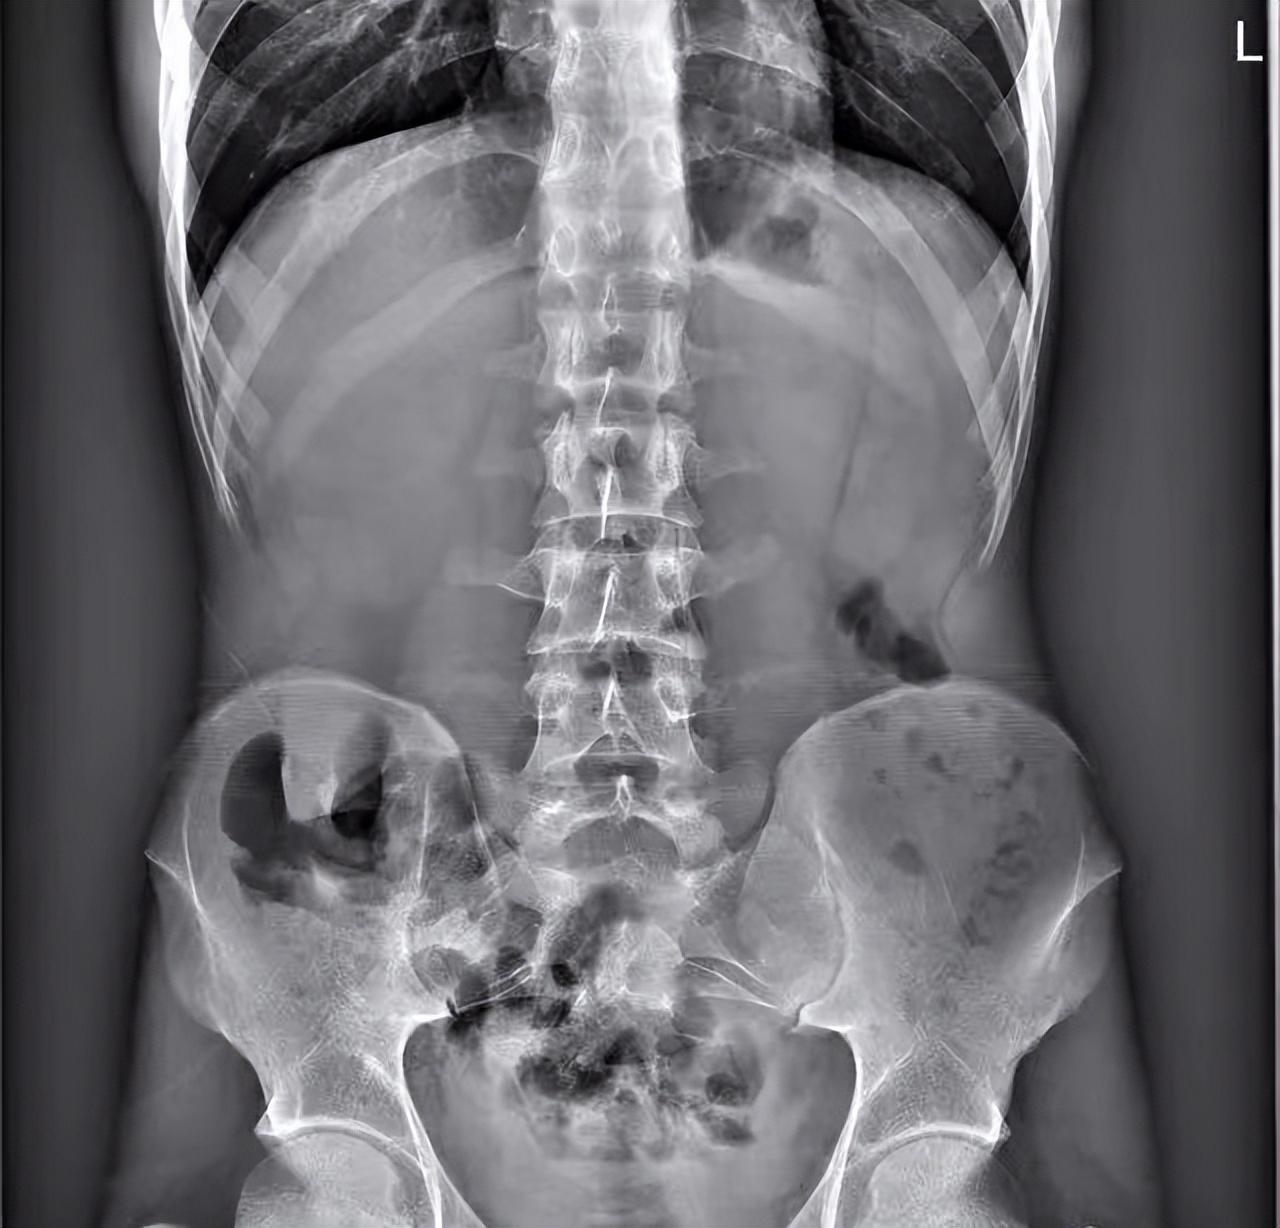

除了从肛门塞进体内的异物外,还有从嘴里吞入奇奇怪怪的异物的案例:就比如有患者有异食癖,在吞入玻璃后,又吞入了图钉...

(图片:图钉位置示意图1)

片子中可以看到,肠道内密密麻麻布满了图钉,超级恐怖!

小看看到这个片子的时候鸡皮疙瘩都起来了...

(图片:图钉位置示意图2)

幸运的是,数百颗图钉在消化道里都没有造成胃肠道穿孔。

经过保守治疗后患者基本恢复正常。